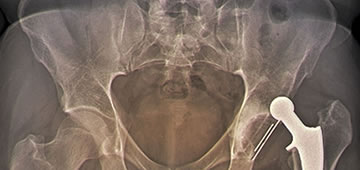

La artroplastia de cadera es el procedimiento quirúrgico mediante el cual se reemplaza la articulación de la cadera por un elemento artificial, conocido más comúnmente como prótesis, que suele estar compuesto de titanio u otras aleaciones metálicas. Existen muchos tipos de artroplastias de cadera, si bien la artroplastia total cementada suele ser la mejor opción a la hora de realizar esta intervención quirúrgica.1 La elección a la hora de colocar un tipo de prótesis u otra responde al tipo de lesión que ha propiciado la cirugía, así como la edad y características del paciente y los propios criterios del cirujano.

Este tipo de intervención es una de las más comunes dentro de la cirugía traumatológica, y se estima que en todo el mundo se realizan unas 300.000 cirugías de artroplastia de cadera al año.1,2 Debido a esto, y pese a ser una cirugía de gran complejidad, la gran mayoría de estas intervenciones salen adelante sin contratiempos, siendo el índice de mortalidad uno de los más bajos en toda la cirugía traumatológica (23 muertes cada 40.000 cirugías, un 0,0006 %), y normalmente estos casos suelen deberse a otras complicaciones o patologías asociadas que el paciente pudiera presentar, como trastornos de coagulación, infecciones, patologías malignas.